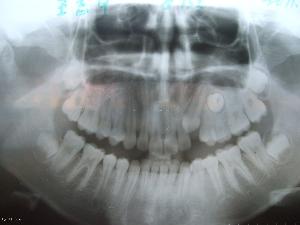

埋伏牙與其周圍組織之間存在牙囊組織,一般是無炎症的。埋伏牙有一種向牙齒胎面及切端方向移動的自然趨勢,遇到阻礙時則產生壓力。埋伏一段時間之後,牙冠釉質表面的成釉上皮會萎縮消失,其上可能有來自牙囊的牙骨質沉積。偶見埋伏牙的牙體組織發生置換性吸收,易誤認為齲齒。

埋伏牙臨床多見於第三磨牙,其次為上頜尖牙,第二雙尖牙和額外牙等,有時有雙側的埋伏牙。一般由X光片檢查發現。在上頜中切牙之間,常有額外牙埋伏,可使兩個中切牙之間間隙加寬。埋伏牙可對相鄰的牙齒產生壓迫症狀,如第二磨牙受埋伏的第三磨牙壓迫,發生牙根吸收,引起疼痛並繼發牙髓炎和根尖周炎。偶見多年戴總義齒的老年患者,有埋伏牙的萌出。